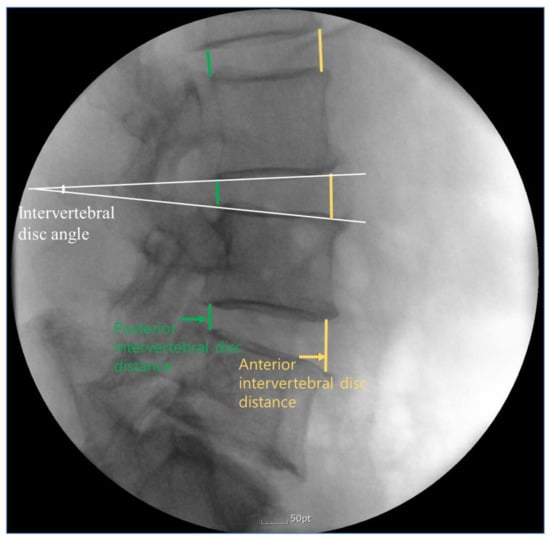

The following items were measured by one blinded specialist in radiology: intervertebral disc angle of all segments, and intervertebral disc distances of anterior and posterior side (Figure 2). Intervertebral disc distance was defined as the distance between the inferior endplate of the upper vertebra and superior endplate of the opposing lower vertebra. Intervertebral disc angle was defined as the angle between the inferior endplate of a superior vertebral body and the superior endplate of the inferior vertebral body in lateral view.

Figure 2. Illustration showing the measurement of intervertebral disc angle at L3/4 level, and intervertebral disc distance of anterior and posterior side.